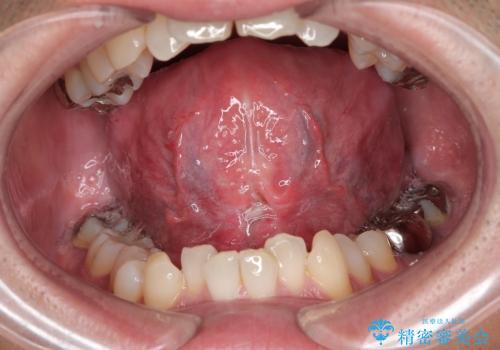

サーフィンで前歯をぶつけて歯が欠けた|かかりつけ医で治療困難と言われ当院へ来院|VPT(生活歯髄療法)で神経を保存|前歯の見た目も改善

[ セラミック治療 ] 前歯の見た目を改善したい

担当医 大元洋佑